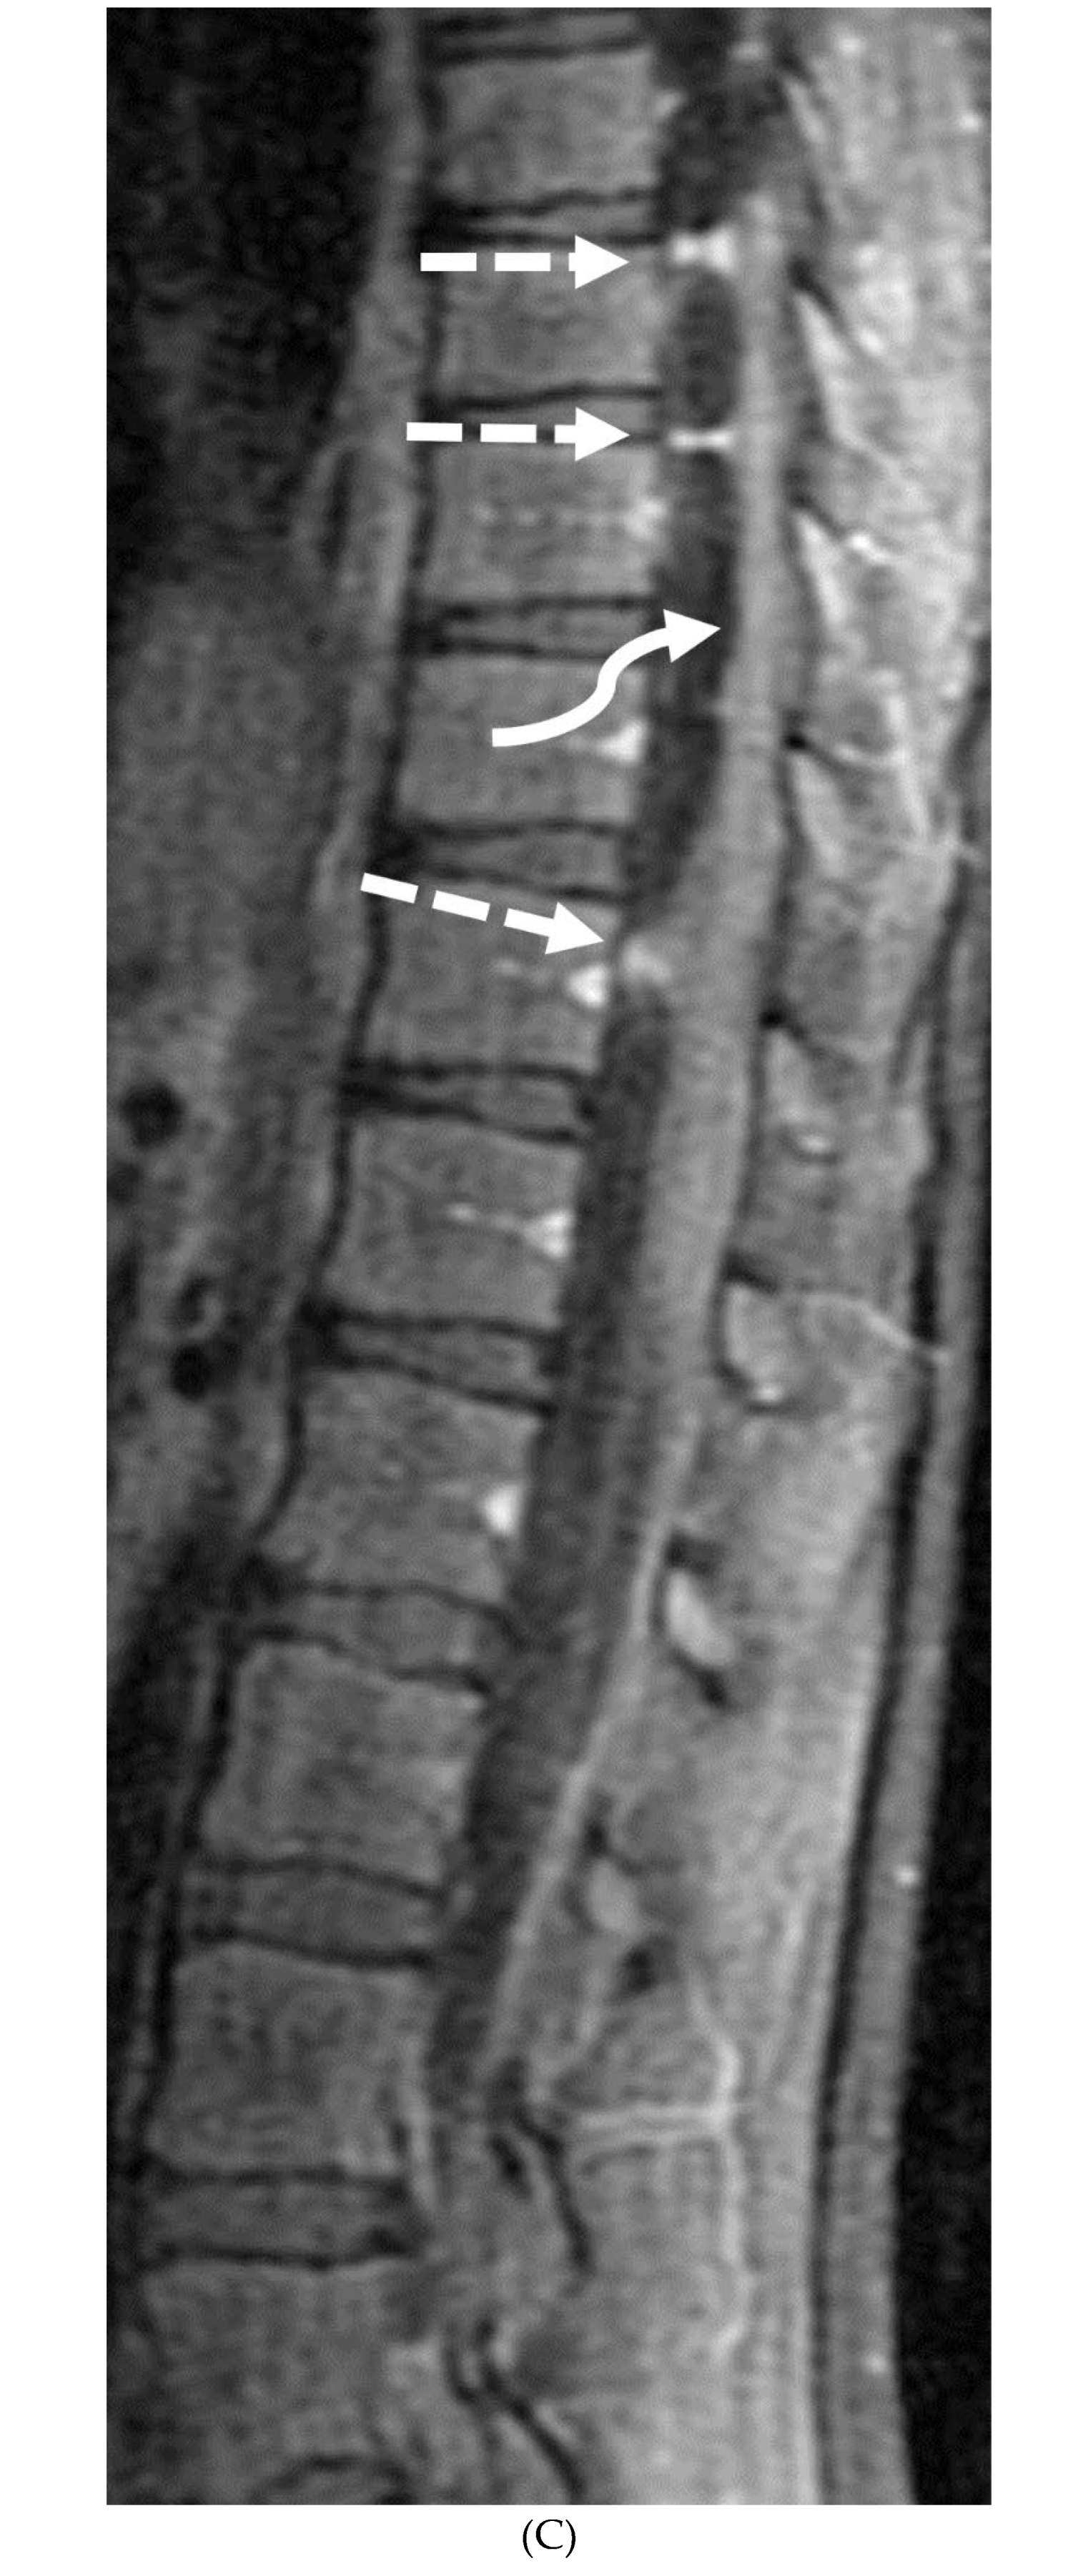

- Alkan O, Yildirim T, Tokmak N, Tan M. Spinal MRI findings of guillain-barré syndrome. J Radiol Case Rep. 2009;3(3):25-8. Epub 2009 Mar 1. PMID: 22470650; PMCID: PMC3303301. [CrossRef]

- Byun WM, Park WK, Park BH, Ahn SH, Hwang MS, Chang JC. Guillain-Barré syndrome: MR imaging findings of the spine in eight patients. Radiology. 1998 Jul;208(1):137-41. PMID: 9646804. [CrossRef]